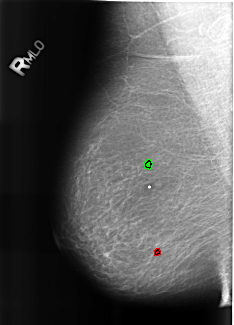

B_3187_1.RIGHT_MLO

FILE: B_3187_1.RIGHT_MLO.OVERLAY

TOTAL_ABNORMALITIES 2

ABNORMALITY 1

LESION_TYPE CALCIFICATION TYPE LUCENT_CENTER DISTRIBUTION N/A

ASSESSMENT 2

SUBTLETY 3

PATHOLOGY BENIGN_WITHOUT_CALLBACK

TOTAL_OUTLINES 1

BOUNDARY

ABNORMALITY 2